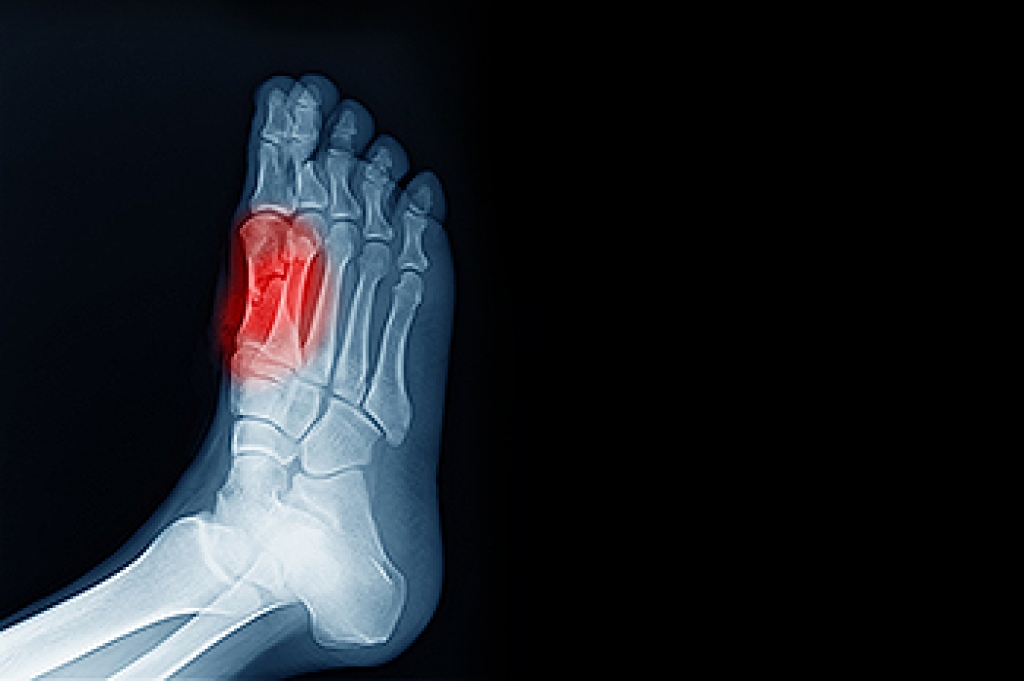

Arthritis is a form of joint inflammation that can find its way into the feet, bringing discomfort and challenges to mobility. Osteoarthritis, often linked to wear and tear, can lead to pain and stiffness in the foot's joints. Rheumatoid arthritis, an autoimmune disorder, can cause painful swelling and deformities. Gout, characterized by sudden, intense pain, emerges from uric acid buildup. Relief options encompass a range of strategies. Wearing custom orthotics, which offer cushioning and support, can help to reduce pressure on affected areas. Stretches and exercises can enhance flexibility and strength. Medications, including anti-inflammatories, can be beneficial in providing relief. Lifestyle adjustments, such as weight management and choosing proper footwear, can also alleviate symptoms. Consulting a podiatrist ensures a tailored approach to managing arthritis in the feet. If you have any type of foot arthritis, it is suggested that you contact this type of doctor who can offer you effective relief options.

Arthritis is a joint disorder that involves the inflammation of different joints in your body, such as those in your feet. Arthritis is often caused by a degenerative joint disease and causes mild to severe pain in all affected areas. In addition to this, swelling and stiffness in the affected joints can also be a common symptom of arthritis.